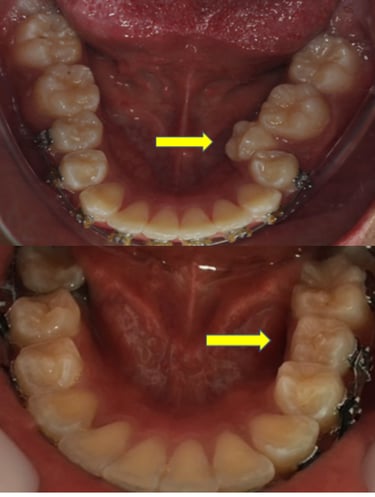

EVOLUÇÃO